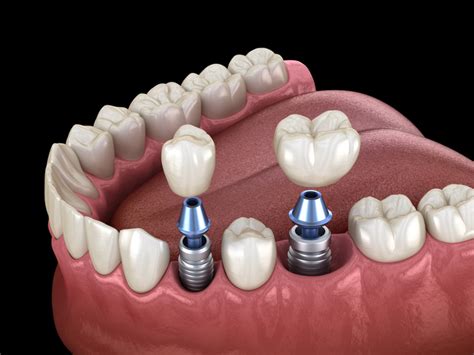

Los implantes dentales permiten reponer las ausencias dentarias de una forma definitiva y altamente predecible. Para reponer dientes con estabilidad similar o incluso superior a la de los naturales perdidos, evitando utilizar dientes adyacentes. Rehabilitar la boca funcional y estéticamente con calidad y precisión.

- Conservación del hueso: El implante no daña piezas vecinas y conserva el hueso.